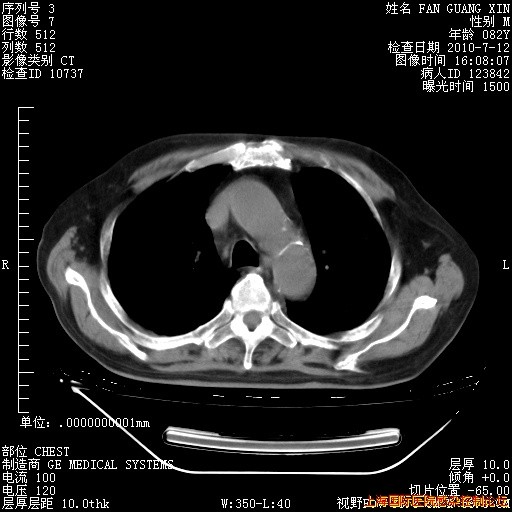

今天CT

整整相隔30天的肺部CT好像有所好转啊。甲强龙减量第3天,需要观察体温。